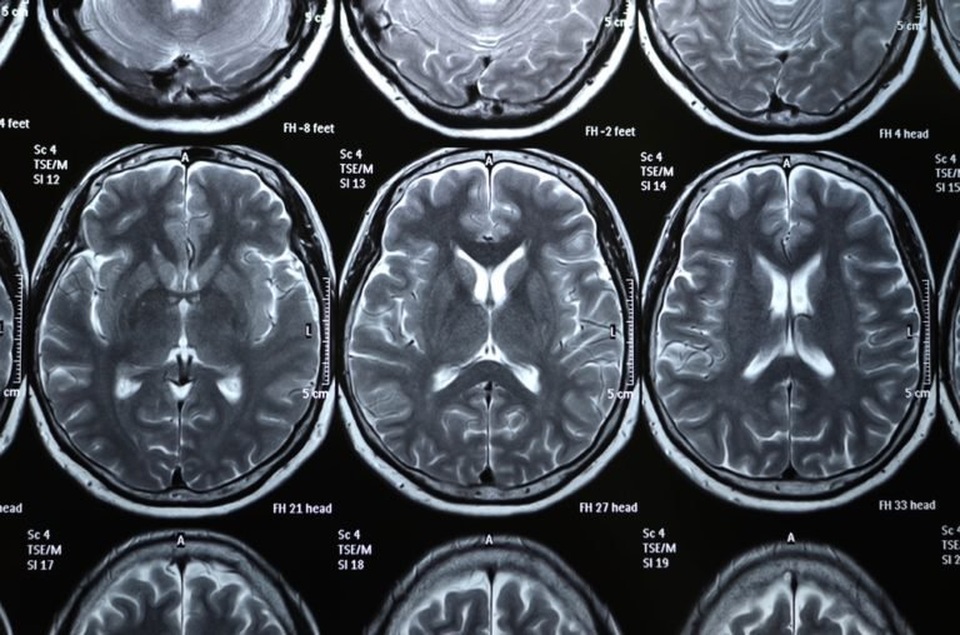

Đột quỵ

Là nguyên nhân gây tử vong thứ năm ở Mỹ, cứ sau bốn phút lại có người chết vì đột quỵ ở nước này, theo Hội Đột quỵ Mỹ. Đột quỵ xảy ra khi cục máu đông gây tắc mạch máu (hoặc vỡ mạch máu) trong não, cắt đứt nguồn oxy đến não. Trong trường hợp đột quỵ do thiếu máu cục bộ (nhồi máu não), các loại thuốc phá huyết khối có thể cứu tính mạng bệnh nhân, nhưng cần phải dùng trong vòng ba giờ.